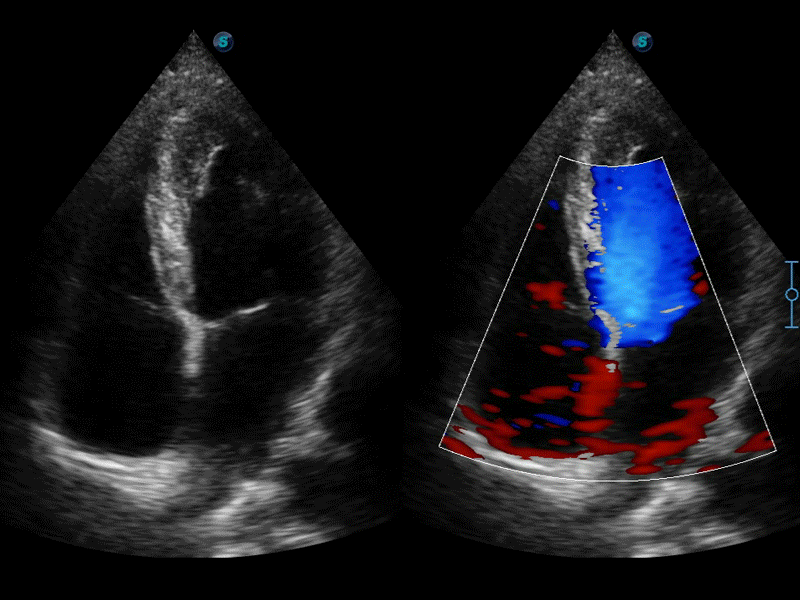

• 心内膜自动描迹Auto EF

自动识别收缩和舒张末期心肌内膜,自动计算射血分数EF值。